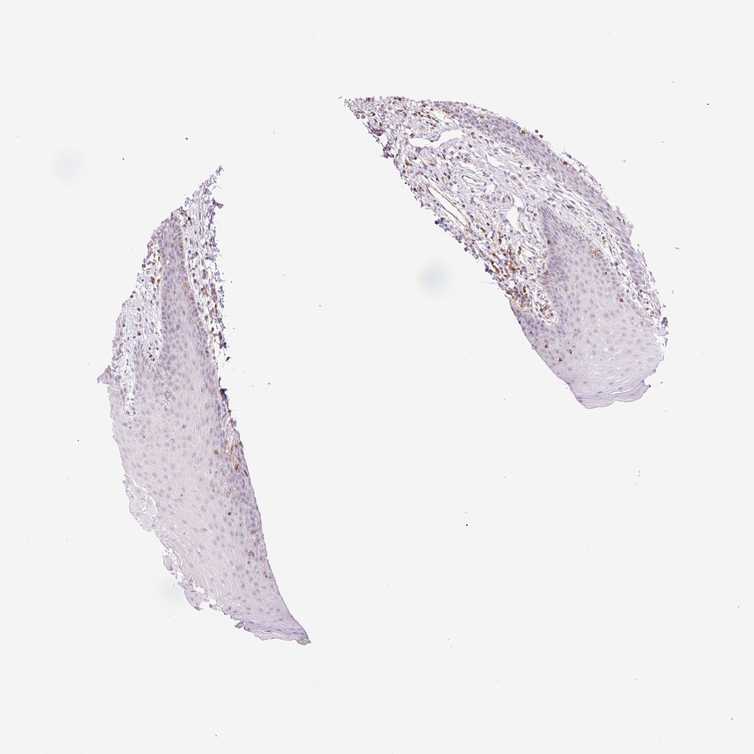

TISSUE PRIMARY DATA ORAL MUCOSA Show tissue menu

ORAL MUCOSA - Antibody stainingi

Antibody staining in the annotated cell types in the current human tissue is reported as not detected, low, medium, or high, based on conventional immunohistochemistry profiling in selected tissues. This score is based on the combination of the staining intensity and fraction of stained cells.

Each image is clickable and will lead to virtual microscopy that enables deeper exploration of all samples and also displays staining intensity scores, fraction scores and subcellular localization as well as patient and tissue information for each sample.

Antibody HPA041454Antibody CAB002509

Squamous epithelial cells Not detectedNot detected